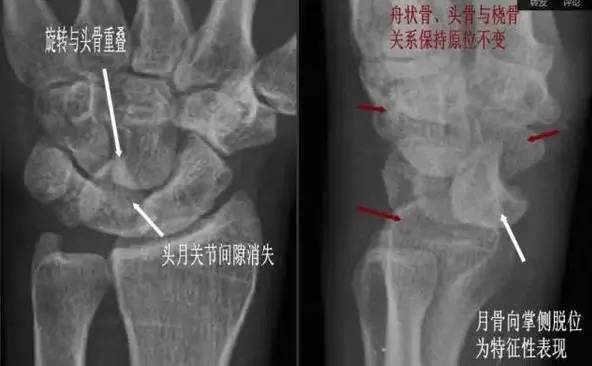

(1)月骨脱位:正位片示月骨由四边形变成三角形或橘瓣状,并向尺侧移位。侧位月骨前移、旋转,窝状关节前空虚。

△ 月骨脱位影像特点

(3)月骨周围脱位:表现为腕关节缩短,头骨与桡骨距离变近,头骨、钩骨与月骨部分重叠,月骨形态及位置基本正常。

△ 月骨周围脱位影像特点